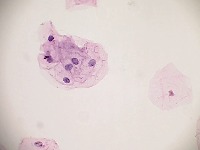

Cervical Cancer Screenings: The "PapDetector" can be used for the initial screening in detecting cervical cancer. Its ability to classify different cellular structures could provide invaluable assistance in large-scale cervical cancer screening tests, making the entire process more efficient.

Medical Research: Scientists and researchers can use this model to identify and further study these cellular structures. This could improve the understanding of various conditions related to cell abnormalities, thus leading to new treatments or diagnostic methods.

Training Medical Students: The "PapDetector" can also serve as a learning tool for medical students, enabling them to visually learn and identify cell structures that denote normal and abnormal cases.

Pharmaceutical Development: The computer vision model could be utilized in the pharmaceutical industry to screen the effects of drug treatments on cell morphology – highlighting normal, HSIL, LSIL, ANORMAL, Koilocytes changes in response to pharmaceutical compounds. This information would be useful in drug development and efficacy trials.